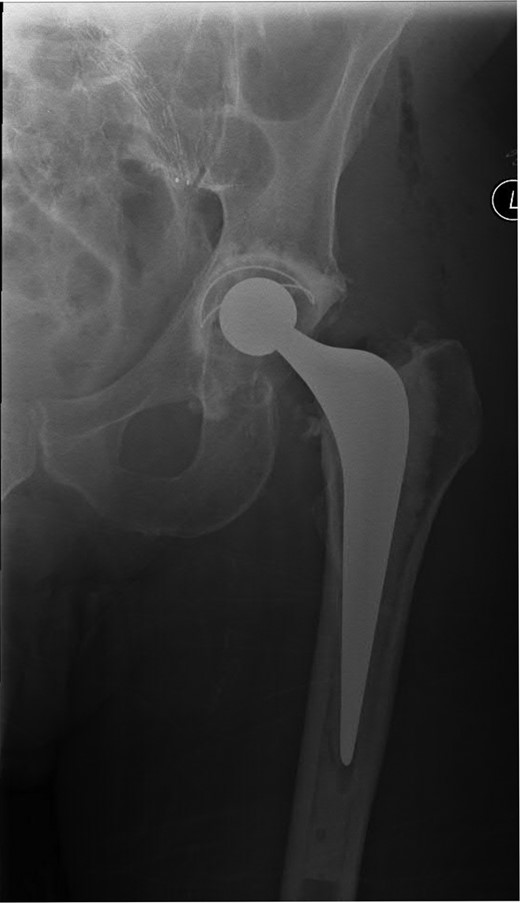

A 74-year-old male was admitted with an intracapsular fractured left neck of femur (Fig. 1). According to the NICE guidelines, he received a cemented THR (Fig. 2) via the posterior approach in the lateral decubitus position. Five weeks prior, he had an EVAR for a leaking AAA. Due to a calcified, narrow right common iliac artery (CIA), the EVAR consisted of a left aortouniiliac endograft with coil embolization of the right CIA and a femoro-femoral crossover graft (Figs 3 and 4).

AP radiograph of the lumbar spine demonstrating the aortouniiliac EVAR with coil embolization of the right CIA.